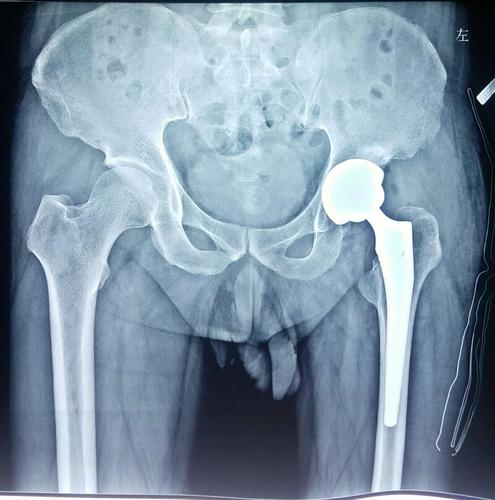

82岁人工半髋置换术

股骨颈骨折半髋关节置换

股骨颈骨折半髋关节置换术后